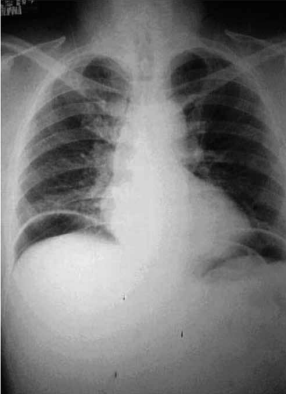

Homem, 69 anos, tabagista, com histórico de uso crônico de AINEs por osteoartrite, apresenta dor epigástrica súbita, intensa, há 4 horas, irradiando para dorso. Ao exame: abdome em tábua, dor à descompressão brusca, sinal de Jobert presente. PA 116/77 mmHg, FC 108 bpm, febre de 38,2ºC. Leucograma com 16.000/mm3 , lactato: 3,5 mmol/L. Radiografia de tórax em ortostase demonstrada na imagem a seguir.

(https://www.researchgate.net/)

Qual é a conduta mais apropriada?